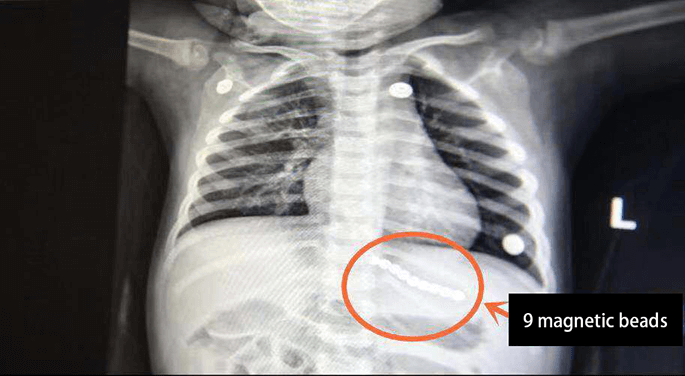

9 magnetic beads in the esophagus of 2 years old child

The 2 year old child in Nanjing swallowed magnetic beads and has been sent to the local hospital for treatment. The child is treated in Nanjing Children Hospital. The worst situation happened. The magnetic beads passed the first natural narrowness glottis and passed the second natural narrowness, then it penetrated the mediastina and penetrate the stomach.